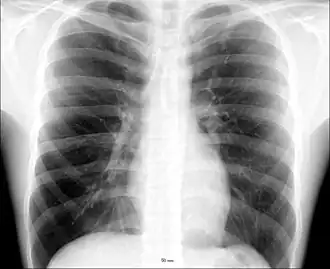

The thorax (pl.: thoraces or thoraxes)[1] or chest is a part of the anatomy of mammals and other tetrapod animals located between the neck and the abdomen.[2][3]

The human thorax includes the thoracic cavity and the thoracic wall. It contains organs including the heart, lungs, and thymus gland, as well as muscles and various other internal structures. The chest may be affected by many diseases, of which the most common symptom is chest pain.

In humans and other hominids, the thorax is the chest region of the body between the neck and the abdomen, along with its internal organs and other contents. It is mostly protected and supported by the rib cage, spine, and shoulder girdle.

The contents of the thorax include the heart and lungs (and the thymus gland); the major and minor pectoral muscles, trapezius muscles, and neck muscle; and internal structures such as the diaphragm, the esophagus, the trachea, and a part of the sternum known as the xiphoid process. Arteries and veins are also contained – (aorta, superior vena cava, inferior vena cava and the pulmonary artery); bones (the shoulder socket containing the upper part of the humerus, the scapula, sternum, thoracic portion of the spine, collarbone, and the rib cage and floating ribs).

Different types of diseases or conditions that affect the chest include pleurisy, flail chest, atelectasis, and the most common condition, chest pain. These conditions can be hereditary or caused by birth defects or trauma. Any condition that lowers the ability to either breathe deeply or to cough is considered a chest disease or condition.

Injury to the chest (also referred to as chest trauma, thoracic injury, or thoracic trauma) results in up to 1/4 of all deaths due to trauma in the United States.[7]

The major pathophysiologies encountered in blunt chest trauma involve derangements in the flow of air, blood, or both in combination. Sepsis due to leakage of alimentary tract contents, as in esophageal perforations, also must be considered. Blunt trauma commonly results in chest wall injuries (e.g., rib fractures). The pain associated with these injuries can make breathing difficult, and this may compromise ventilation. Direct lung injuries, such as pulmonary contusions (see the image below), are frequently associated with major chest trauma and may impair ventilation by a similar mechanism.